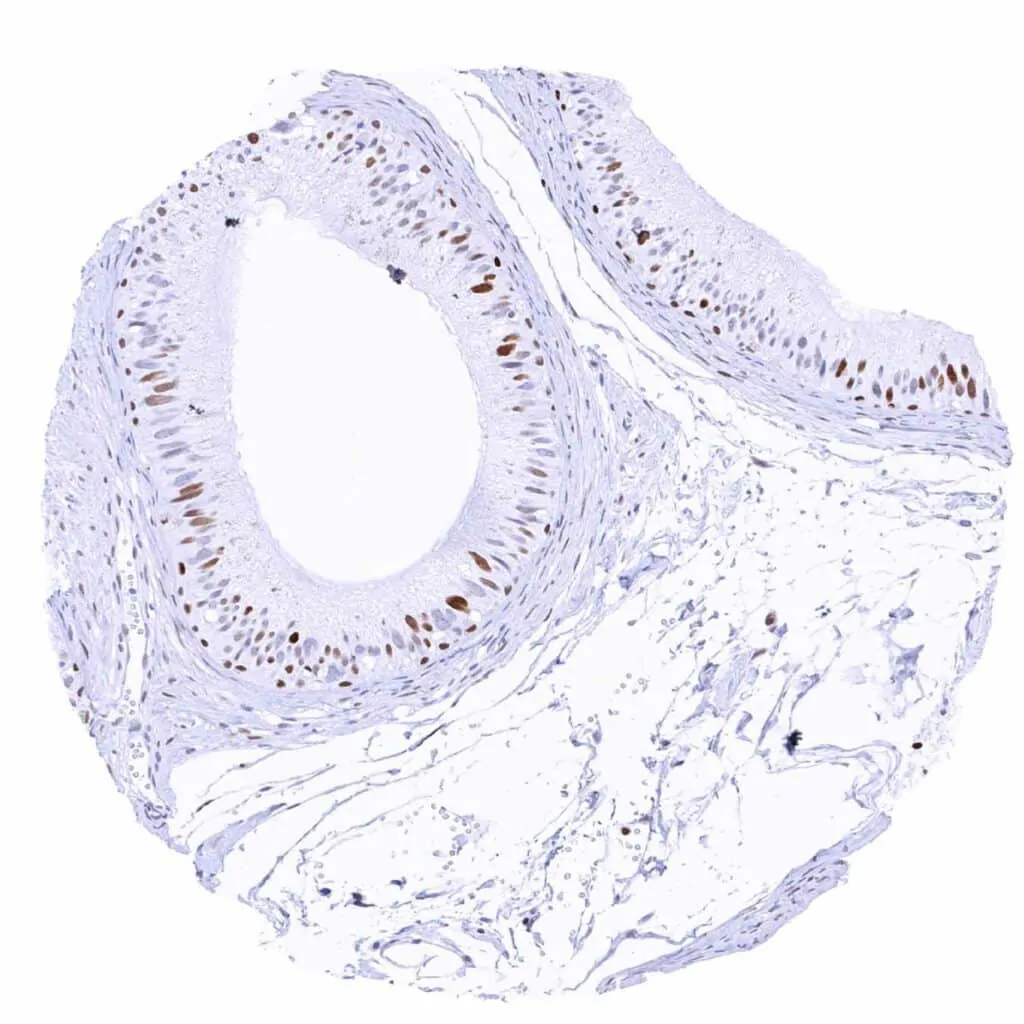

Urinary bladder, urothelium – Some (suprabasal) urothelial cells show a MCM2 staining